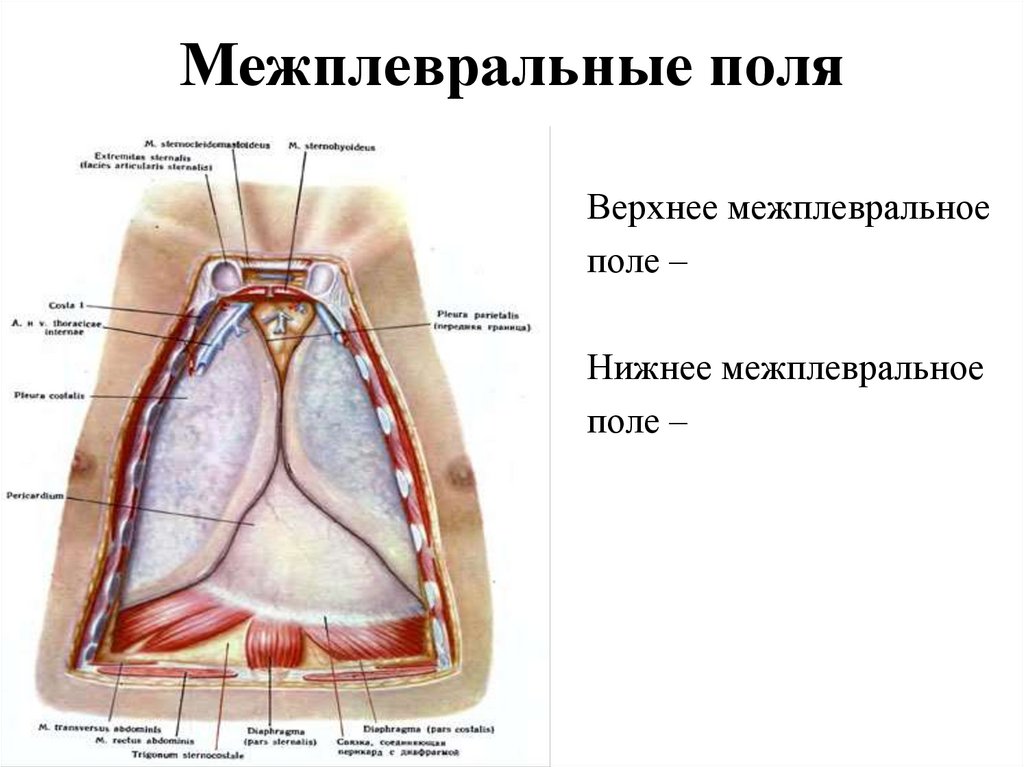

Анатомия межплеврального пространства